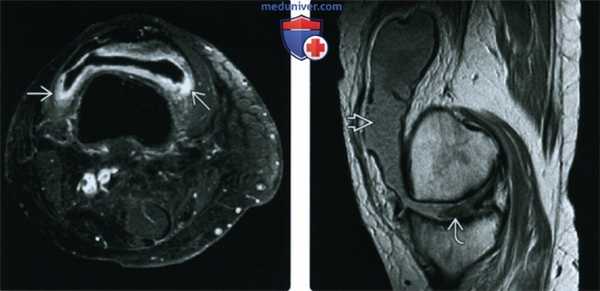

(Слева) Рентгенография в ПЗ проекции: склероз и эрозии крестцово-подвздошных суставов. Поражение двухстороннее, но асимметричное: слева более выражено, чем справа. Тем не менее, не забывайте, что у пациента с ХРА может наблюдаться симметричное поражение на любой стадии заболевания.

(Справа) Рентгенография в ПЗ проекции: тяжелые изменения при ХРА с двухсторонним анкилозом крестцово-подвздошных суставов. Визуализируется одностороннее эрозивное поражение тазобедренного сустава. При длительном течении заболевания патологический процесс может затрагивать проксимальные суставы. (Слева) Рентгенография в боковой проекции: выраженные эрозии заднего отдела пяточного бугра. Плотность костной ткани нормальная. Признаки типичны для ХРА, но не патогномоничны. Они могут наблюдаться, хотя и с меньшей вероятностью, и при других эрозивных артритах, таких как РА, ПСА и АС.

(Справа) Рентгенография в боковой проекции: типичная картина ХРА с реактивными изменениями и энтезопатией в местах прикрепления ахиллова сухожилия и подошвенного апоневроза. Такие реактивные изменения не должны иметь место при РА или АС. (Слева) Рентгенография левой пяточной кости пациента с ХРА в боковой проекции: изменений нет, отчетливо выражены кортикальный слой и предахиллесово жировое тело. Рентгенография представлена для сравнения.

(Справа) Рентгенография противоположной пяточной кости у этого же пациента в боковой проекции: размытость кортикального слоя и начальные эрозивные изменения. Предахиллесово жировое тело замещено воспалительной тканью. Это ранняя стадия заболевания, признаки которого на рентгенограмме могут быть выражены слабо и, потому, требуют всестороннего анализа.